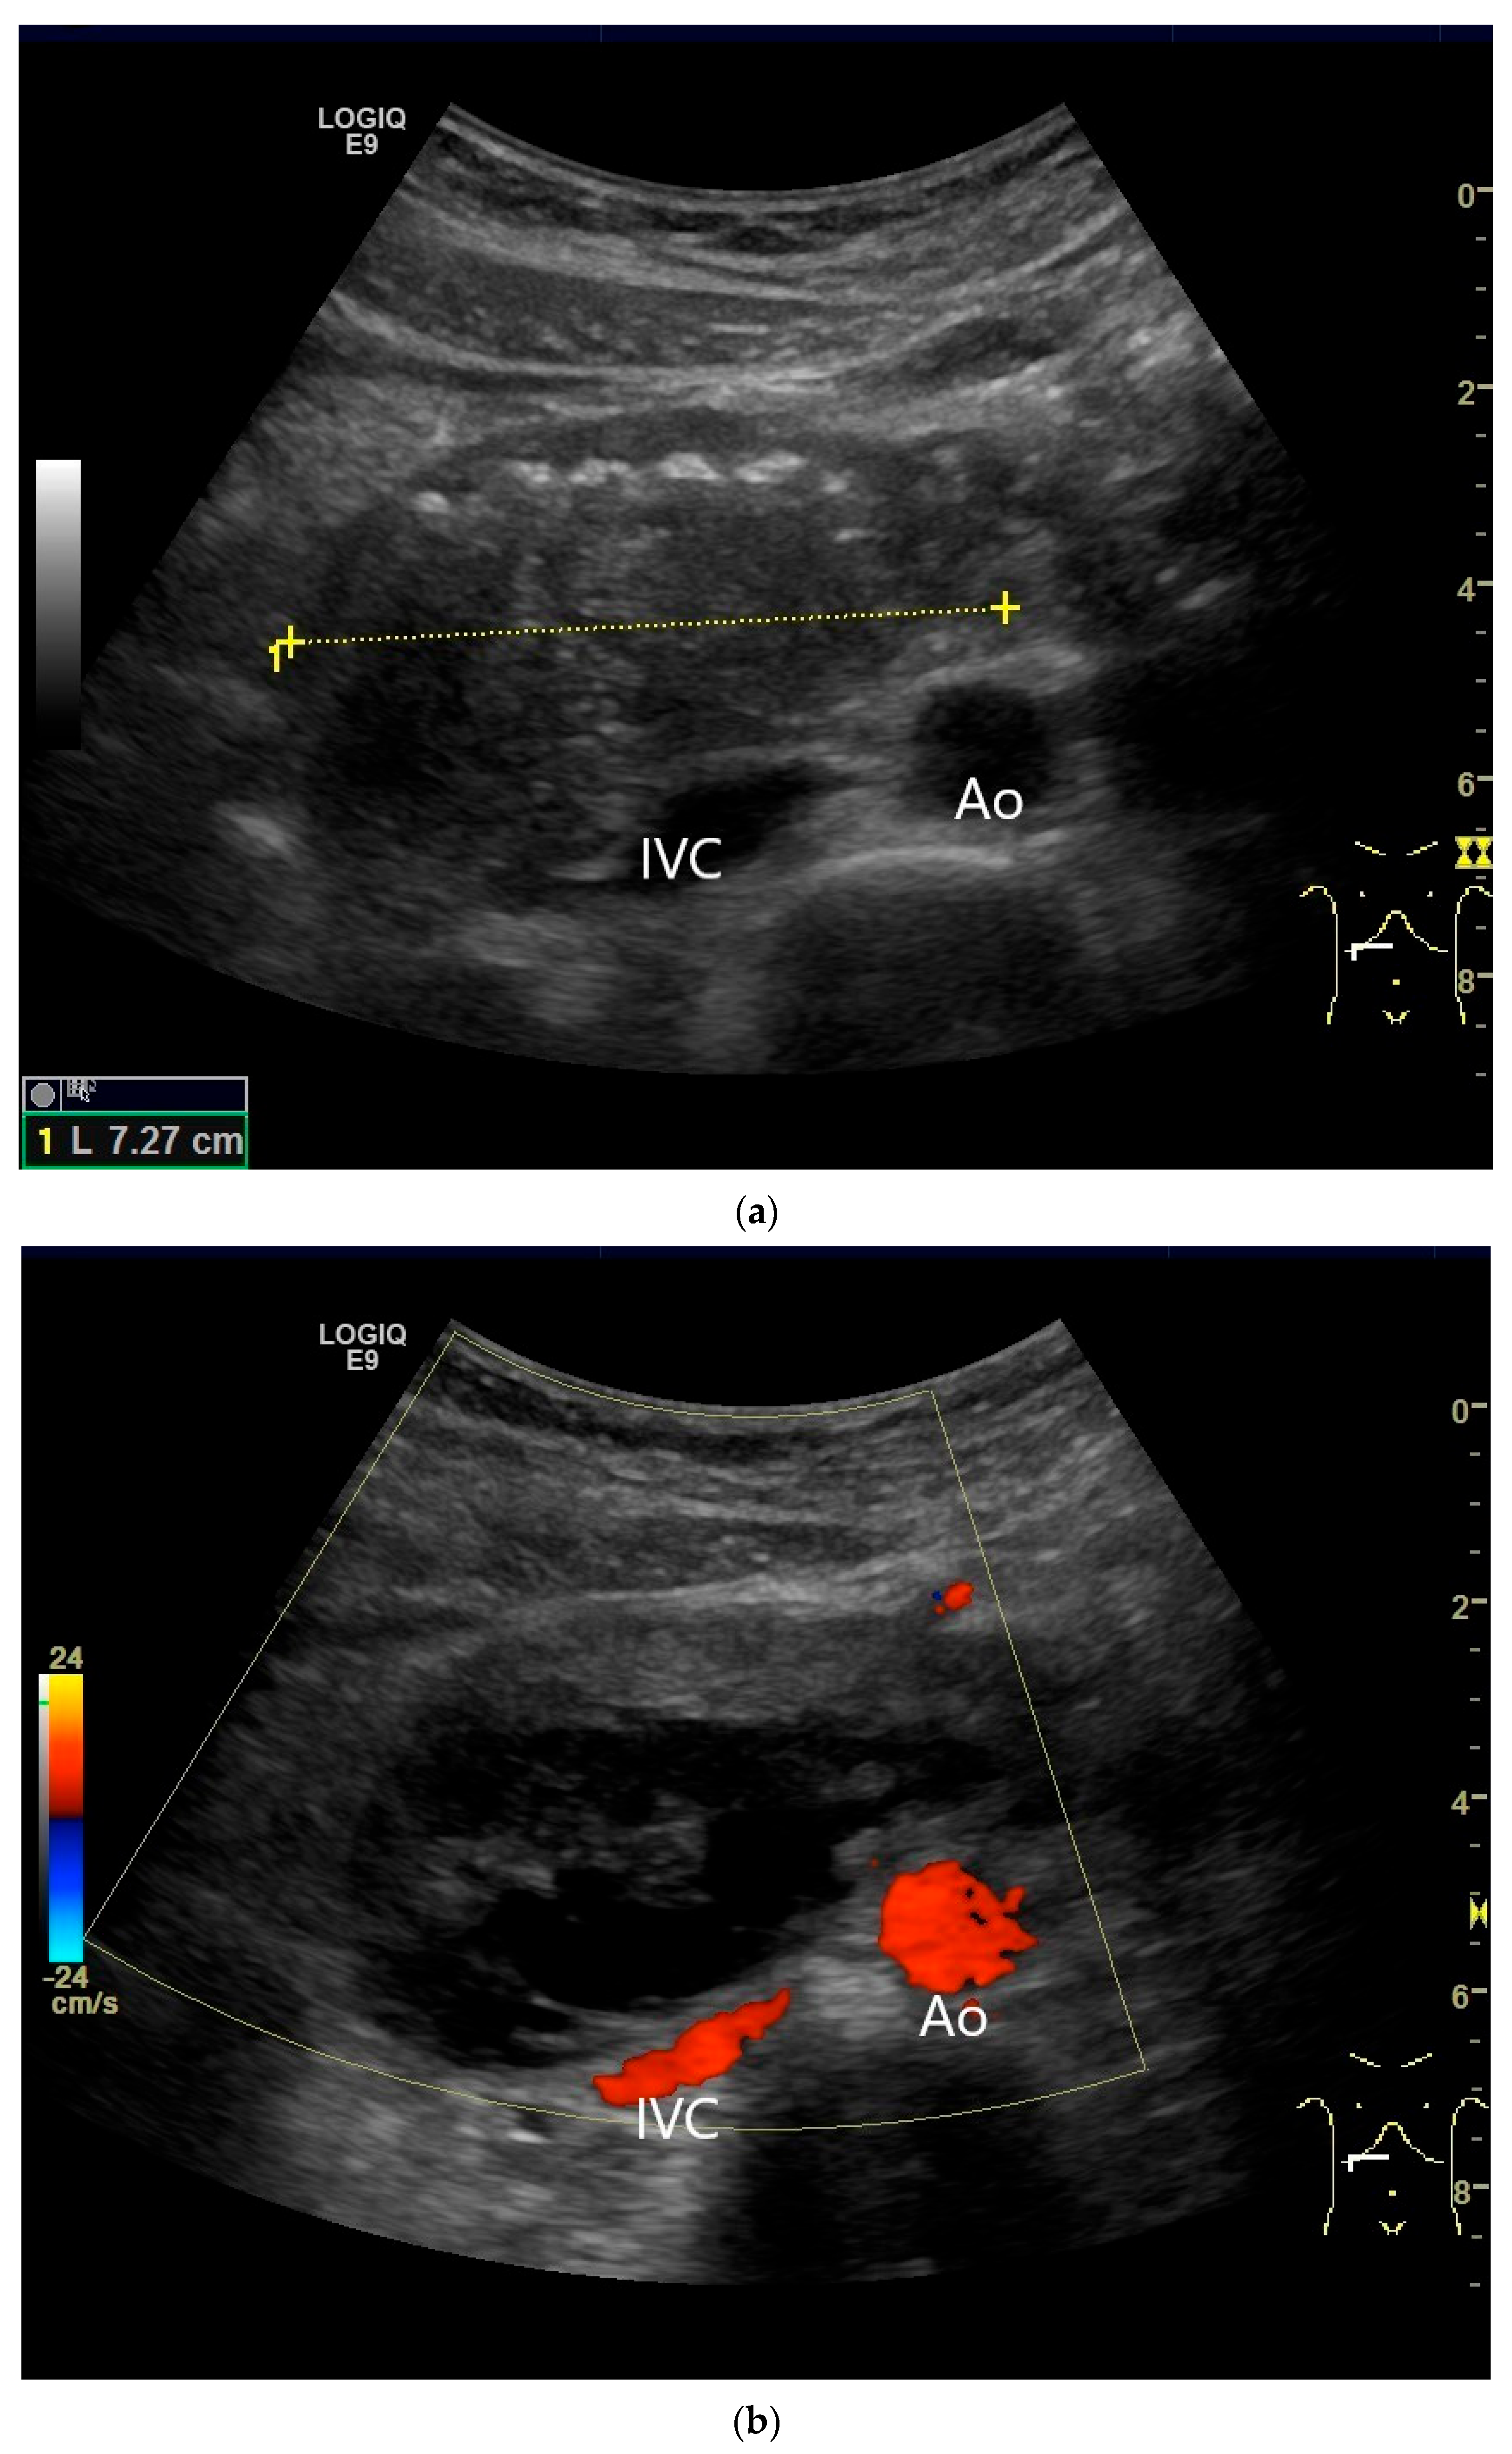

Figure 21.

Duodenal wall hematoma after gastroscopy with forceps biopsy under dual antiplatelet therapy. Clinically, there was pain and lumen obstruction. Evident focal hypoechoic wall thickening (between the markers) with lumen obstruction (a), for which there was no correlation in the previous gastroscopy. No evidence of macro vessels in CDI (b). In CEUS, the mass is smoothly defined and completely non-enhanced (c). IVC—inferior caval vein, Ao—aorta.